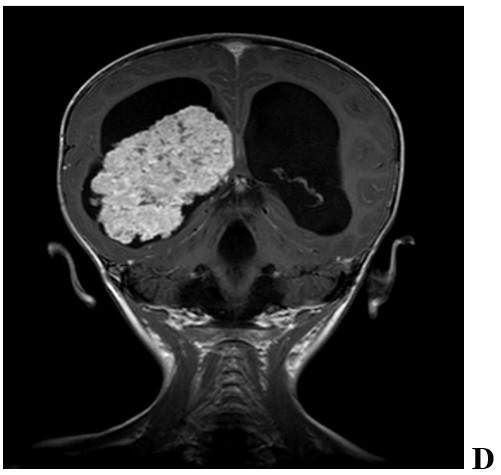

We have done an initial CT, showing a massive expansive process in right lateral ventricle with calcifications and hyper vascular. Also, we found hydrocephalus with periventricular edema (Figure 1). Examination with MRI presents signs of hyper productive hydrocephalus. The right lateral ventricle is much larger than the left and contains a large lobular mass located in the trigonum. The tumor manifested with low-hypointense signal at T1 generally lower than that of cerebral parenchyma but higher than that of CSF. The images in T2 (Figure 1) showed high signal (microcalcifications are presented with hypo signals). After application of IV contrast they showed pronounced signs of pathological vascularization (Figure 2).

Figure 2.

Radiographic features of a pediatric CPP in 2 year old female. We found significant hydrocephalus (A-F) with transependymal flow (F) due to either increased production of CSF or obstruction by tumor debris and blood products. Intraventricular and/or intratumoral hemorrhage are not uncommon. CPPs enhance on T1-weighted MRI with contrast (C,D and E) due to their rich vascular supply. They are generally iso-or hypointense on T1-and T2-weighted MRI (A, B and F) but may demonstrate heterogeneous hyperintensity in some cases. Magnetic resonance angiography may aid in visualizing the tumor’s vascular supply (C, D and F)